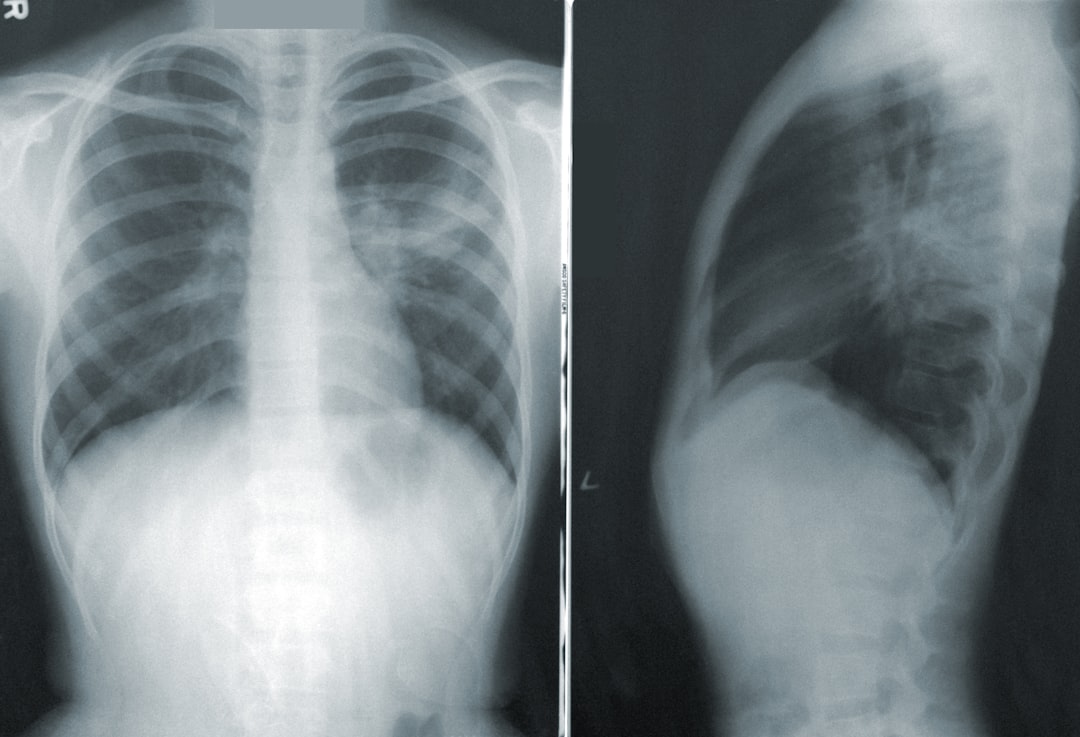

- Diagnose av tørrbensykdom kan gjøres ved hjelp av røntgen, MR, eller CT-skanning for å vurdere beinvevet.

Diagnosen av tørrbensykdom begynner vanligvis med en grundig medisinsk historie og fysisk undersøkelse. Legen din vil spørre om symptomene dine, inkludert når de begynte og hvor alvorlige de er. Deretter vil det bli utført bildediagnostiske tester for å vurdere tilstanden til beinvevet.

Røntgenbilder kan gi en første indikasjon på osteonekrose, men mer detaljerte bilder som MR (magnetisk resonansavbildning) er ofte nødvendig for å bekrefte diagnosen. MR-skanninger er spesielt nyttige fordi de kan vise tidlige tegn på osteonekrose før endringer blir synlige på røntgenbilder. I noen tilfeller kan legen din også anbefale blodprøver for å utelukke andre medisinske tilstander som kan forårsake lignende symptomer.

En tidlig diagnose er avgjørende for å kunne iverksette riktig behandling og forhindre ytterligere skade på beinvevet.